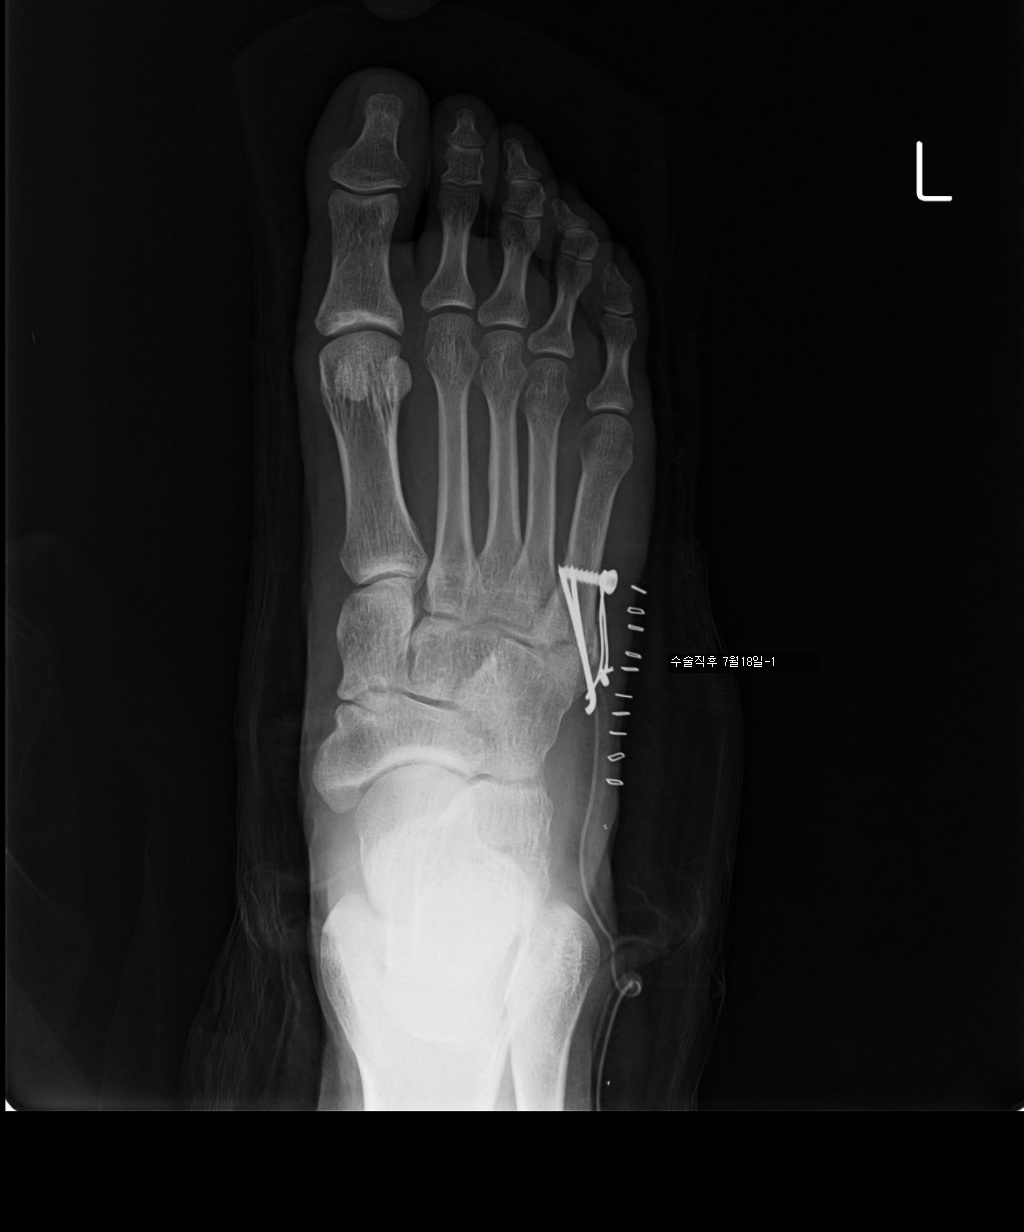

수술한지 100일 정도 됩니다.

7/17 : 출근 중 지하철 계단에서 구르는 사고로 좌측제5중족골기저부 골절

7/18 : 관헐적 정복 및 금속내고정술  시행 및 반깁스 (2주)

아래는 그간의 사진입니다. 제 눈은로는 수술직후의 사진과 3개월후의 사진의 차이를 잘 모르겠네요..